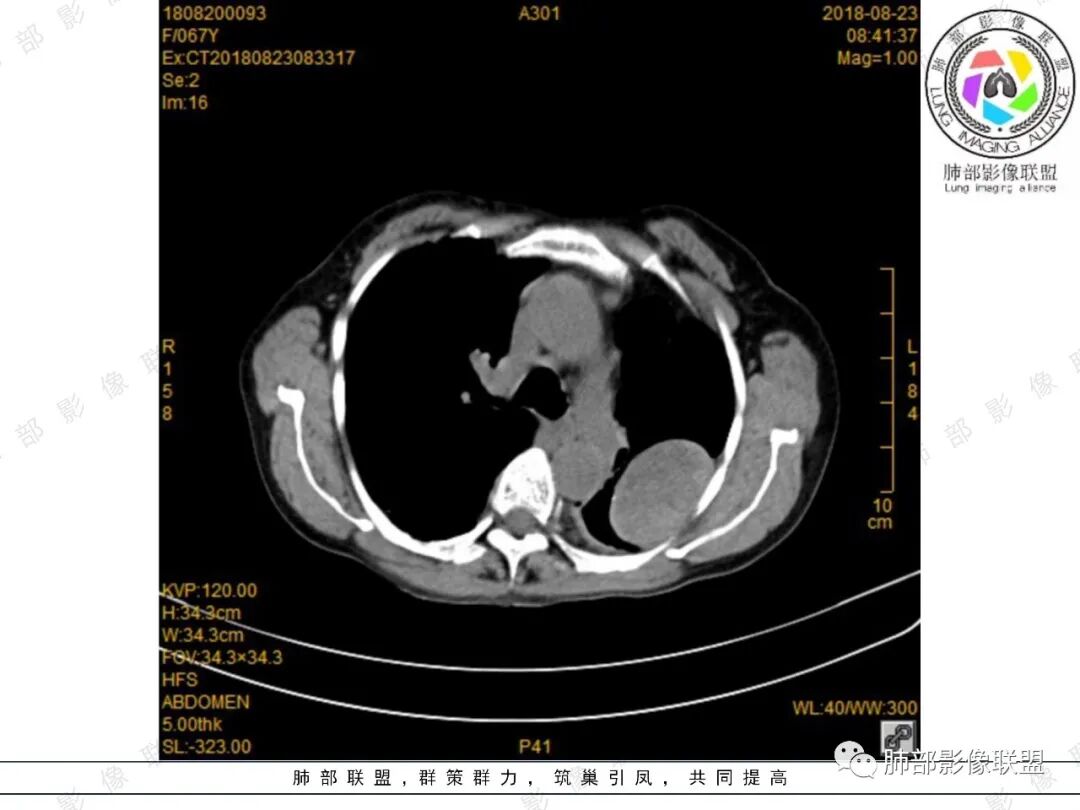

采莲:中年女性,有便血病史,左肺上叶椭圆形肿块,边缘光滑,长轴与胸膜平行,与胸膜宽基底相连,内部密度较均匀,有低密度区,密度较高,强化不明显,脊柱旁胸膜增厚,有便血病史,不知道是不是慢性,考虑来源胸膜,髓外造血?脾脏不会看。其他神经源性肿瘤?

小强:脾大,延迟强化均匀,无明显占位,左胸膜下孤性增厚,局限性膨大,强化不均匀,先考虑EMH,不太支持的是临近骨质没有膨大。

看图说话:左肺肿块,边缘光滑,密度不均匀,不均匀强化,胸腔少量积液,纵隔肿大淋巴结。脾脏增大,见肿块影,不均匀强化,一元论,考虑淋巴瘤,转移瘤。

月亮圆了!:左肺上叶胸膜下肿块,宽基底与胸膜相连,边缘清晰,局部肺组织受压,支气管显示不佳,平扫密度不均匀,增强后,可见轻度不均匀强化,纵隔光滑,无分叶,无毛刺,周围组织无牵拉,收缩,内部有不均匀低密度,脾脏明显肿大,脾内多发类圆形低密度影,增强后,轻度强化,有便血,考虑可能:1:淋巴瘤2:脾梗死。

傅昌瑜:定位肺外,定性因为有脾脏占位有点困难,一元考虑恶性肿瘤并脾脏转移(神经内分泌肿瘤?),二元的话,胸部病灶考虑神经源性肿瘤,鞘瘤可能性大,SFT待排。

杨丽:老年女性,宽基底及胸膜掀起,考虑肺外病灶,供血动脉看不太不清,中等不均匀强化,首选sft;脾大,较均匀强化肿块,一元论考虑转移机会大,也不好除外二元论,淋巴瘤?

joyzhy:脾脏占位增大,特点延迟期强化和脾脏一致,考虑血管瘤。胸部占位,考虑肺外,鞘瘤或髓外造血。